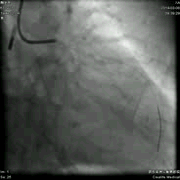

左冠造影:左主干末端偏心性、钙化狭窄,程度95%。 前降支开口狭窄80%,中段弥漫性叉口病变,狭窄85%,远段血管纤细,TIMI血流2级。中间支起始部局限性扩张。 回旋支开口狭窄70%,近中段弥漫性叉口病变,狭窄85%。

![]()